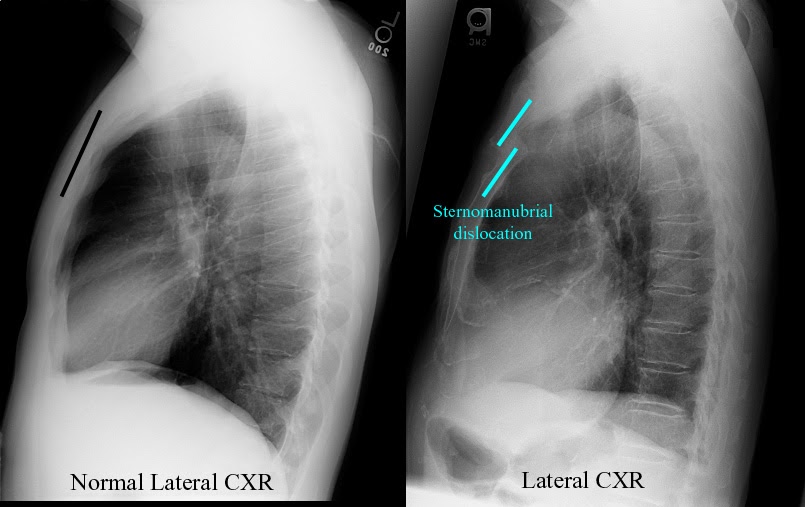

Normal lateral sternum Radiology Case Radiology How To Do A Sternum X Ray This view is invariably undertaken for one of two reasons, to assess for a fracture or metastasis. The sternum (breastbone) is a flat bone, vertically oriented at the midline of the anterior aspect of the thorax. the lateral sternum view a radiographic investigation of the entire length of the sternum in profile. In fact every radiologst should be an.. How To Do A Sternum X Ray.